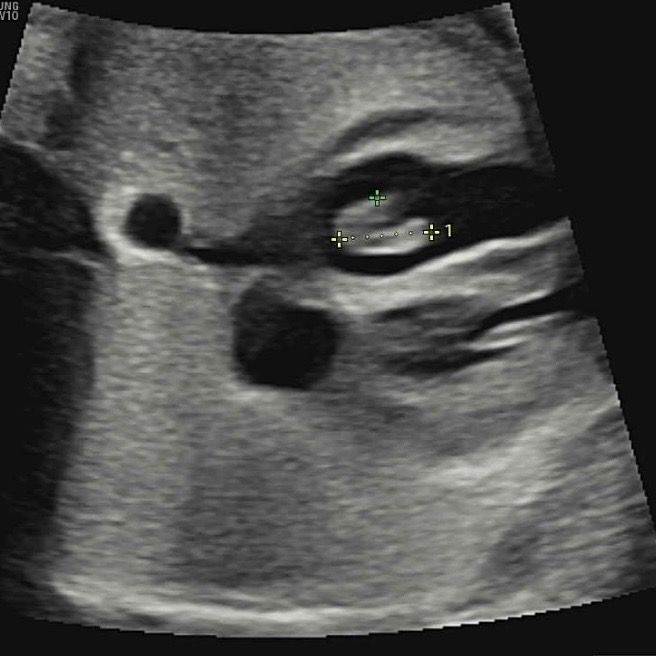

두번째로는 이제껏 깨끗하게 보였던 태아 심장에서 하얀 덩어리가 보이는데 혹같다고 말씀하시더라구요~ 일단 낳고 보자시는데 다른 개인병원 방문했을땐 또 안보인다 하셔서 불안해요. 한번 봐주세요ㅠㅠ

• 1번 째 사진